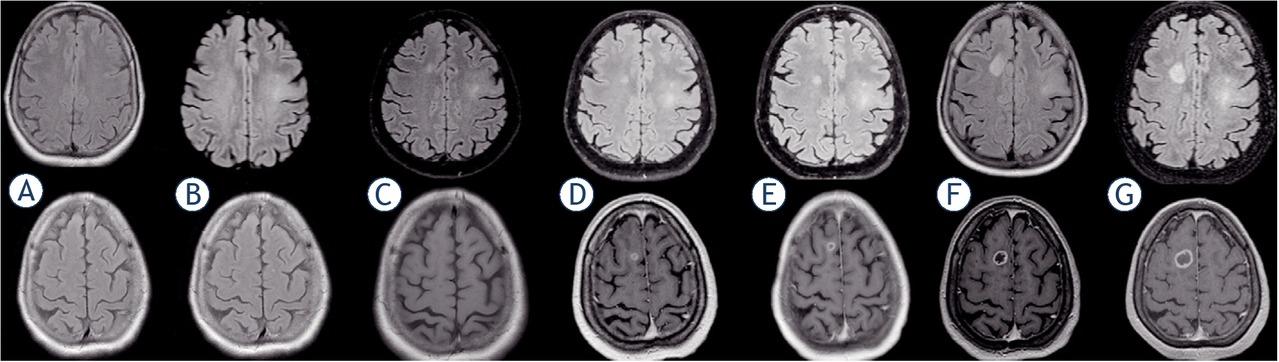

A 72 y.o. female patient, after a seizure, underwent MRI workout without pathological findings. She repeated a MRI scan after 15 months and a FLAIR alteration in the left motor areas was seen. MTD was 21.25 mm. She refused any treatment. MRI scan was repeated further 9 months later showing a bilateral alteration of FLAIR signal in the frontal lobes. MTD was 26.30 mm. However, the patient chose to undergo neuroradiological follow-up rather than surgery. After two months, a new MRI scan showed an EN in the right frontal lobe. MTD of EN was 8.43 mm, MTD of FLAIR altered regions was 32.01 mm. Neurosurgeons suggested excision of the EN, but the patient refused again. Further MRI scans at 2, 6 and 10 weeks were obtained. MTD of EN were 11.19, 17.54 and 21.40 mm, respectively. MTD of FLAIR-altered regions were 35.73, 41.68 and 41.68 mm, respectively (Figure 2). At the end complete resection of EN was obtained; histopathological diagnosis was compatible with GBM, IDH1 WT. She underwent adjuvant therapy according to the Stupp regimen and remains alive 31 months after the index surgery. All values of ΔMTD, VDE and Acc calculated according to equations [2], [4,] [5], [6], [7] for every MRI scan are listed in Table 1, divided for FLAIR and EN volumes.

MRI scans in Patient 3 at 0 (A), 465 (B), 742 (C), 790 (D), 811 (E), 825 (F) and 854 (G) days (fluid attenuated inversion recovery [FLAIR] and T1 with gadolinium sequences).